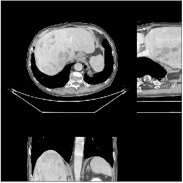

Fig.Β 5 shows the reconstructions and the corresponding error (magnitudes) images (shown for the central axial, sagittal, and coronal planes) for FDK, PWLS-EP, and PWLS-ULTRA () with the patch-based weights. Compared to FDK and PWLS-EP, PWLS-ULTRA significantly improves image quality by reducing noise and preserving structural details (see zoom-ins). Fig.Β 6 shows the RMSE for each axial slice in the PWLS-EP and PWLS-ULTRA (with the weights ) reconstructions. PWLS-ULTRA clearly provides large improvements in RMSE for many slices, with greater improvements near the central slice.

Section IV.E and Table III of [60] compared the performance of various methods for low-dose cone-beam (3D) CT reconstruction, for the XCAT phantom volume. Fig.Β 13 shows the reconstructions and the corresponding error (magnitudes) images (shown for the central axial, sagittal, and coronal planes) at for FDK, PWLS-EP, PWLS-ST (with ), and PWLS-ULTRA () with patch-based weights . PWLS-ULTRA provides better reconstructions and reconstruction errors compared to the conventional FDK and the non-adaptive PWLS-EP. PWLS-ULTRA also outperforms the proposed PWLS-ST scheme, and provides sharper reconstructions of image edges (see zoom-ins).